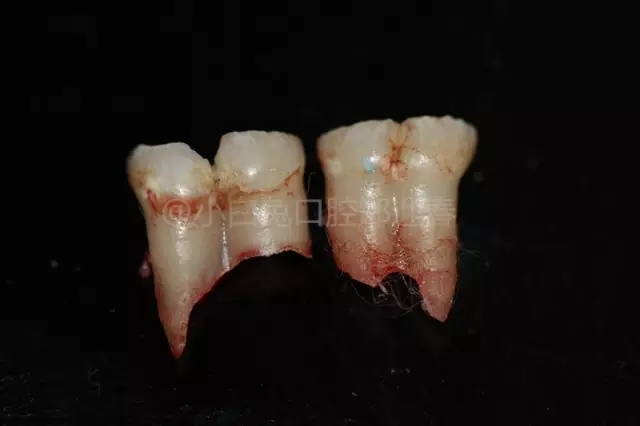

拔出后的離體牙

根據(jù)融合時(shí)間的早晚,可以形成冠根完全融合,也可以形成冠部融合而根部分離,或冠部分離而根部融合,臨床上所見到的多是牙冠部融合,這個(gè)時(shí)候的牙齒可以是一個(gè)根管,也可以是兩個(gè)根管。融合牙不但導(dǎo)致牙齒形態(tài)的異常,影響牙齒的形態(tài)美觀;還可以導(dǎo)致牙列的異常,導(dǎo)致牙體、牙髓、牙周疾病;還可能因?yàn)檠例X排列不整齊,導(dǎo)致咬合關(guān)系的不正常容易引起顳下頜關(guān)節(jié)疾病。

6、由于融合發(fā)生的時(shí)期不同,就會(huì)表現(xiàn)出各種融合的類型:牙冠、牙根和牙髓腔都融合為一的;牙冠融合、牙根分開、髓腔根管各一的;牙冠分開、牙根融合。所融合的兩個(gè)牙,可以都是正常牙,如發(fā)生在乳側(cè)切牙和乳尖牙之間的融合;也可以是正常牙和多生牙之間的融合,例如乳側(cè)切牙和多生牙融合。